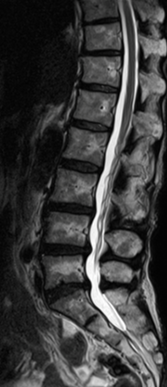

在磁共振领域,深度学习技术对图像进行降噪、上采样、减轻振铃伪影的处理,带来了清晰且细节丰富的图像。

过去,高分辨率图像的获取往往伴随着漫长的扫描时间,这影响了图像获取的效率,对于危重疾病的快速诊断是一大挑战。然而,PIQE技术的出现彻底颠覆了这一局面。此次发布的全新3T磁共振Galan Supreme,搭载全新的自研磁体和梯度线圈,并深度融合PIQE技术,可以实现在不增加扫描时间的前提下,轻松获取到高分辨率的图像,为临床带来了兼具高效与高质量的影像体验。

左右滑动查看更多